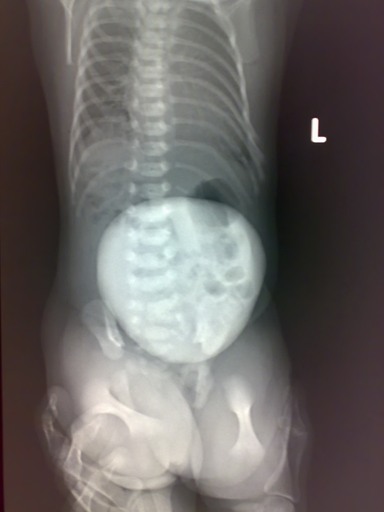

患儿女 生后1小时

下腹部圆形巨大肿块,密度均匀,腹腔脏器结构显示大致正常,考虑膀胱外翻可能。

下腹部区域巨大椭圆形肿块影,边界清楚。是仰卧位还是府卧位?也没有侧位。肿块位于前还是后?

考虑:1、脐疝?2、膀胱外翻?3、脊膜膨出?

小儿腹部类圆形软组织肿块影,边缘光整,密度较高,有没有寄生胎的可能?经常见有寄生胎的报道,患儿的母亲怀孕时可能怀的是双胞胎,一个胚胎在另一个胎儿体内,形成了不完全发育的胚胎组织,但病率较低。脐疝、、膀胱外翻、脊膜膨出不能完全除外。

患儿是住院查体检查,因为病变比较明显,所以只有正位片。

包块位于腹壁。

脊膜膨出可以排除了,正位观察脊柱无明显改变就应该可以排除的。但侧位还是非常重要的,可以观察到肿块的内部结构密度以及跟腹部交界面的关系。

患儿是  脐膨出。

支持!一张正位片也只能考虑这么多,我想它还不如临床体检来的诊断信息多。如果楼主稍微描述一下,大家都会考虑的靠谱一些。既然结果是脐疝。再跟大家复习一下膀胱外翻:

膀胱外翻(泌尿外科)是由于胚胎期泄殖腔膜的发育异常,导致先天性的下腹壁和膀胱前壁缺损,膀胱后壁外翻,粘膜暴露的膀胱畸形。该病罕见,约1-4万新生儿中有一例。男性多于女性,约2-8:1。由于膀胱外翻,膀胱粘膜和输尿管口外露,很易导致尿失禁及上行性的肾孟肾炎,未经治疗者半数死于儿童期。男性患者多合并有尿道上裂,阴茎短小。同时也可以伴有泌尿系统和身体其他部分器官的畸形。

下腹部区域巨大椭圆形肿块影,边界清楚;腹腔脏器结构显示尚可。脐疝、膀胱外翻。